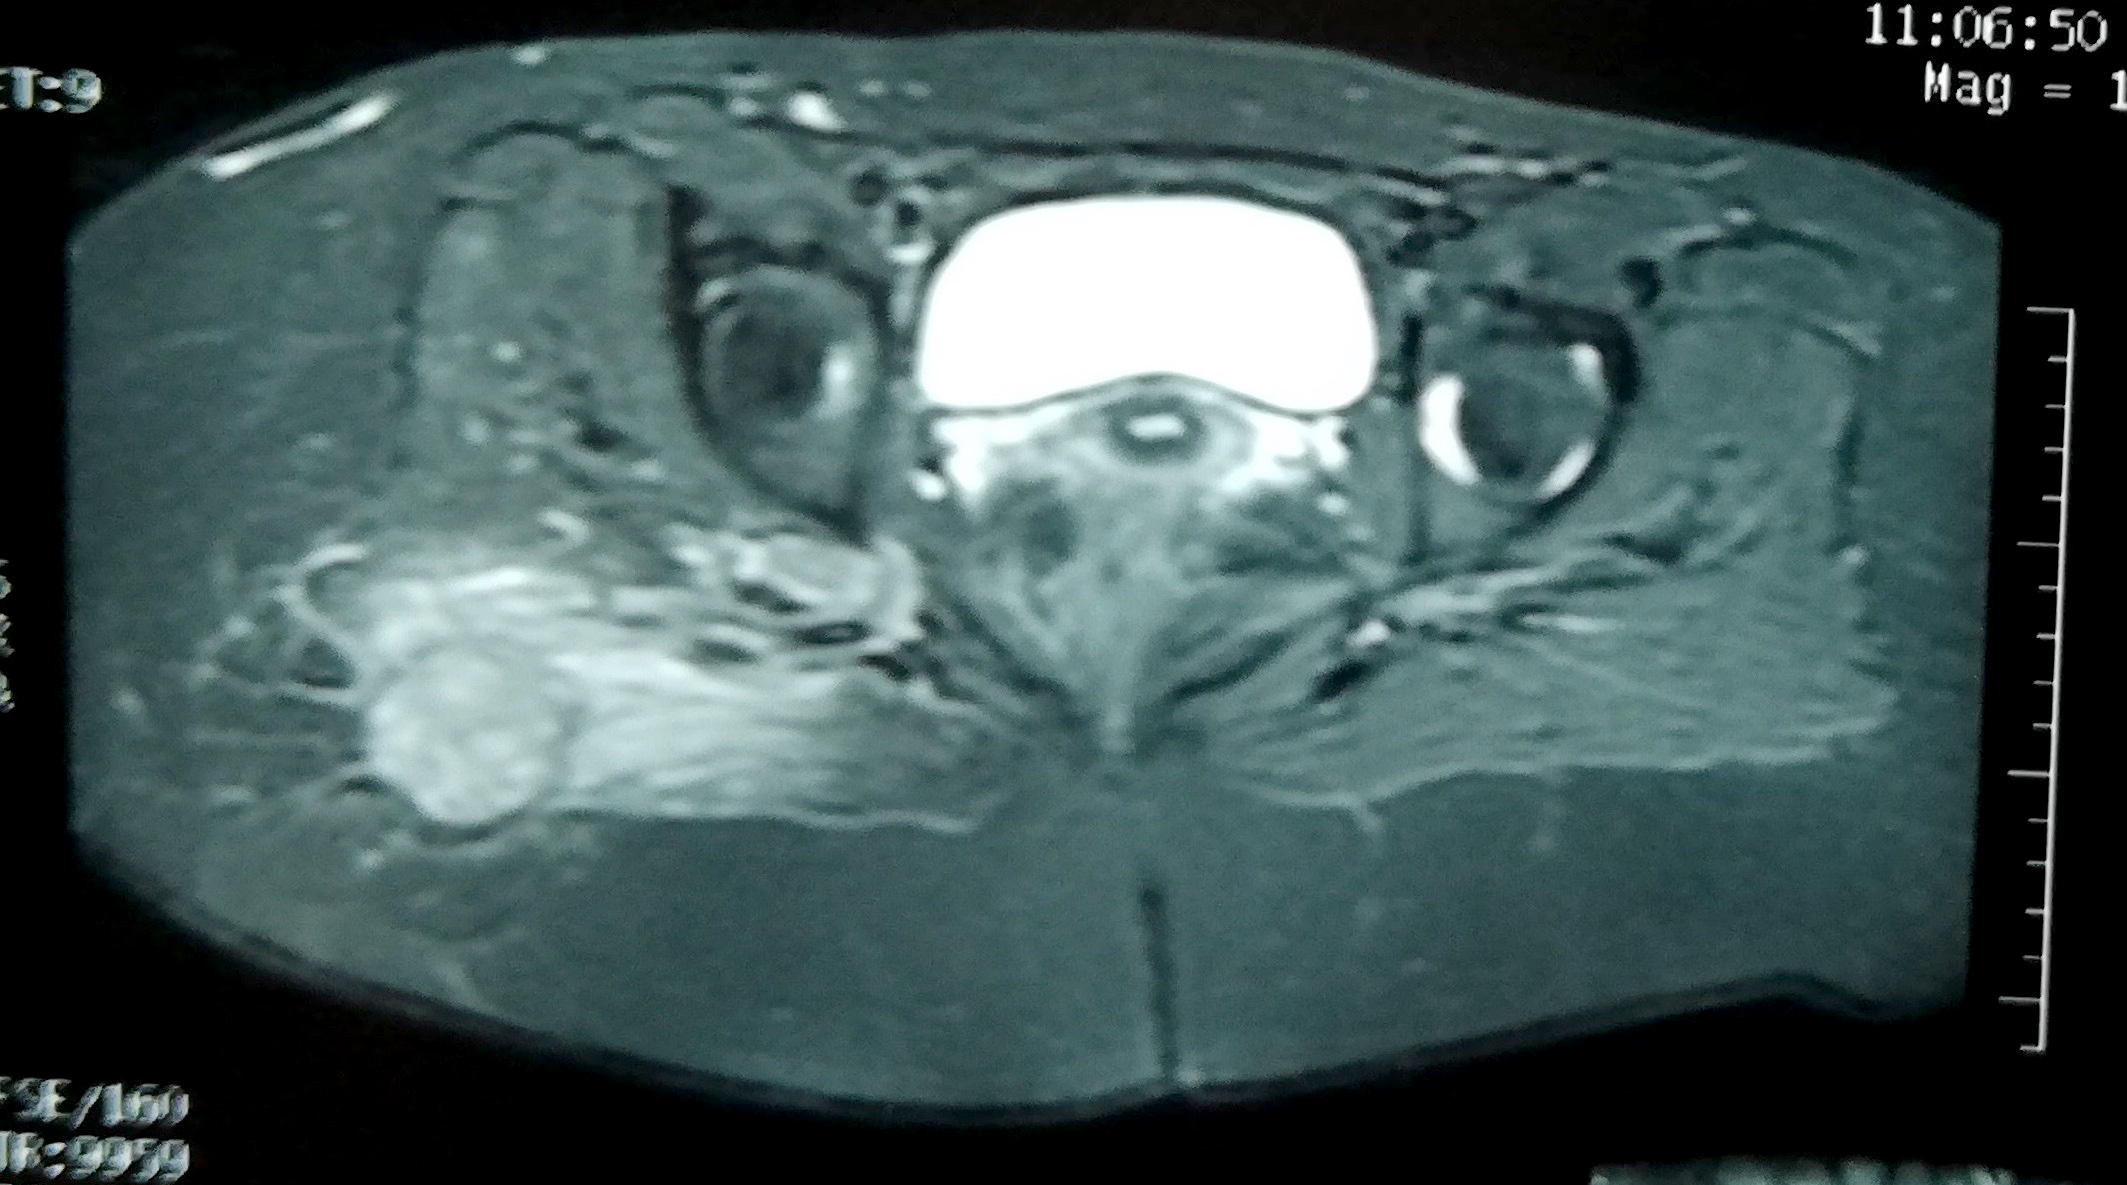

Radiology description

- Early stage:

- Xray: normal to faint calcification (flocculent radiopacities: dotted veil pattern)

- CT scan: soft tissue edema

- MRI: isodense on T1 and hyperintense on T2

- Intermediate stage:

- Xray: peripheral calcified rim with central lucency

- CT scan: peripheral mineralization with central low attenuation (calcification proceeds from periphery to center)

- MRI: isodense / hypodense to adjacent skeletal muscle on all images

- Mature, late stage:

- Xray: diffuse soft tissue calcification

- CT scan: diffuse ossification pattern (even in late lesions, the central core may remain uncalcified)

- MRI: well defined soft tissue mass and isodense to fat on all images

- References: Curr Sports Med Rep 2018;17:290, J Clin Orthop Trauma 2021;17:123

Radiology images